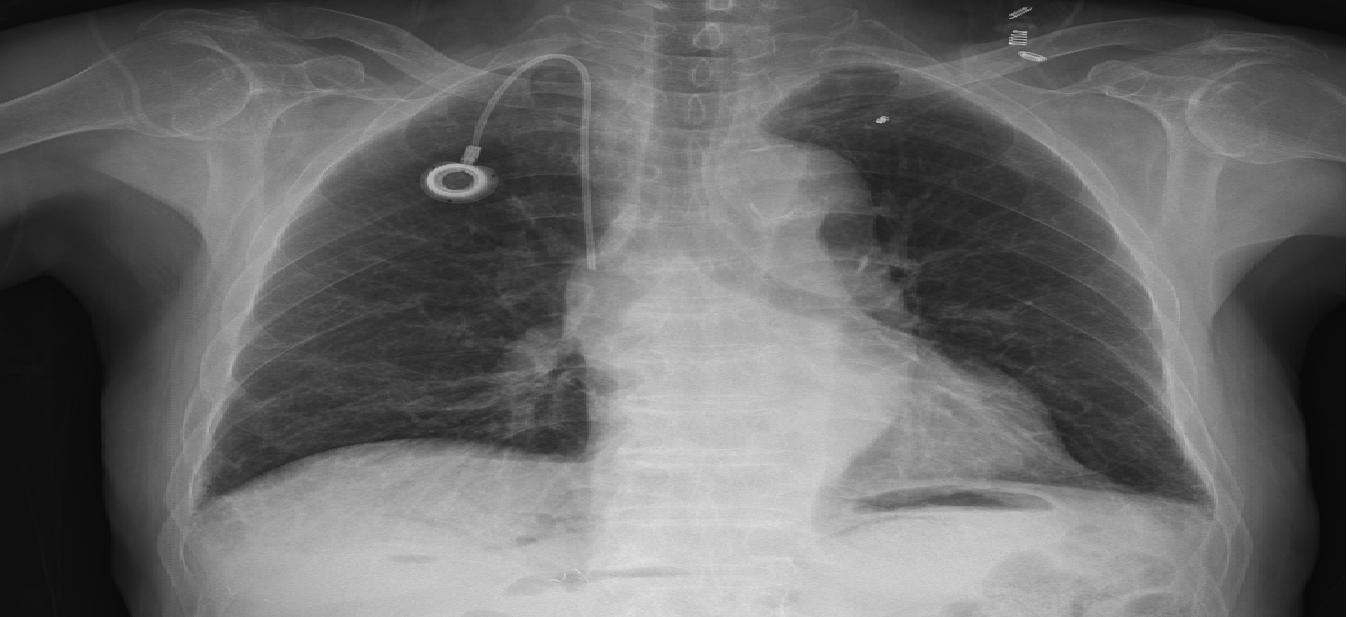

2020๋…„ ์•ˆ์‹ฌํด๋ฆฌ๋‹‰ ์ง„๋ฃŒ๋Š” ์ผ๋ฐ˜ ํ˜ธํก๊ธฐ ๋‚ด๊ณผ์—์„œ ์ง„๋ฃŒ ์ง„ํ–‰ ํ›„ ์ฝ”๋กœ๋‚˜ ํ™•์ง„์ด ์˜์‹ฌ๋  ์‹œ, ๋ณธ๊ด€ ์ถœ์ž…๊ตฌ์— ์žˆ๋Š” ์Œ์••์ง„๋ฃŒ์‹ค์—์„œ ์ง„๋ฃŒ

๋ฐ ํ‰๋ถ€ X-Ray ์ดฌ์˜, ํˆฌ์•ฝ์„ ์ง„ํ–‰ํ•˜์˜€๋‹ค.

๋ฐœ์—ด์ด ์—†์ง€๋งŒ ํ˜ธํก๊ธฐ ์ฆ์ƒ์ด ์žˆ๋Š” ๊ฒฝ์šฐ๋Š” ์™ธ๋ž˜๋กœ ์ง„์ž…, ์Œ์••์‹œ์„ค์ด ์žˆ๋Š” ์•ˆ์‹ฌํด๋ฆฌ๋‹‰ ์ง„๋ฃŒ์‹ค๋กœ ์•ˆ๋‚ดํ•˜์—ฌ ์ง„๋ฃŒ ๋ฐ ํ‰๋ถ€ ๋ฐฉ์‚ฌ์„  ์ดฌ์˜์œผ ๋กœ ํ๋ ด ์—ฌ๋ถ€๋ฅผ ํ™•์ธํ•˜๊ณ  ์ฝ”๋กœ๋‚˜19๊ฐ€ ์˜์‹ฌ๋  ์‹œ ์„ ๋ณ„์ง„๋ฃŒ์†Œ ์žˆ๋Š” ๋Œ€ํ•™๋ณ‘์›์œผ๋กœ ์ด์†กํ•˜์˜€๋‹ค. ์ฝ”๋กœ๋‚˜ ๊ฒ€์‚ฌ๊ฐ€ ํ•„์š”ํ•œ ๊ฒฝ์šฐ์—๋Š” ์‹ ๊ด€ ํ›„ ๋ฌธ ๊ฒ€์‚ฌ์†Œ์—์„œ PCR ๊ฒ€์‚ฌ๋ฅผ ์ง„ํ–‰ํ•œ ํ›„ ๊ท€๊ฐ€ ์กฐ์น˜ํ•˜์˜€๋‹ค.

27์ผ, ๋ณธ์› ๊ฑฐ์  ์ „๋‹ด๋ณ‘์› ์ง€์ • ์ดํ›„์—๋Š” ๋‹จ์ˆœ ์•ฝ ์ฒ˜๋ฐฉ์€ ํ˜ธํก๊ธฐ ํด๋ฆฌ๋‹‰์—์„œ ์ง„๋ฃŒ ์ง„ํ–‰ํ•˜์˜€๊ณ , ํ‰๋ถ€ X-Ray ์ดฌ์˜์ด ํ•„์š”ํ•˜๊ฑฐ๋‚˜ ์ฝ”๋กœ๋‚˜

์ฒ˜๋ฐฉ์•ฝ ๋Œ€์ƒ์ž์ธ ๊ฒฝ์šฐ์—๋Š” ํ™•์ง„์ž ์™ธ๋ž˜์ง„๋ฃŒ์„ผํ„ฐ๋กœ ์ด๋™ํ•˜์—ฌ ์ถ”๊ฐ€ ์ง„๋ฃŒ๋ฅผ ์ง„ํ–‰ํ•˜์˜€๋‹ค. 2022๋…„ 6์›” 24์ผ ์ดํ›„์—๋Š” ํ˜ธํก๊ธฐ ํ™˜์ž ์ง„๋ฃŒ ์„ผํ„ฐ๋กœ ํ†ตํ•ฉํ•˜์—ฌ ์šด์˜ํ•˜์˜€๋‹ค.

ยท ํ‰๋ถ€ X-ray ์ด์ƒ ์†Œ๊ฒฌ

์ดฌ์˜

์ด์ƒ ์†Œ๊ฒฌ ๆœ‰ ์ด์ƒ ์†Œ๊ฒฌ ็„ก

์ฝ”๋กœ๋‚˜ PCR๊ฒ€์‚ฌ ์ง„ํ–‰

PCR ์–‘์„ฑ PCR ์Œ์„ฑ

์ผ๋ฐ˜์ง„๋ฃŒ ์ง„๋ฃŒ ํ›„ ์•ฝ ์ฒ˜๋ฐฉ ์•ˆ์‹ฌ ํด๋ฆฌ๋‹‰ ํ‰๋ถ€์‚ฌ์ง„